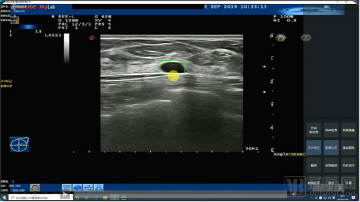

医准智能乳腺超声智能检测系统不需要对设备改动,且不需要调整现有工作流程,在医生扫查病人的同时,AI服务器进行实时分析,并在界面进行标记提示,对于仅毫秒级闪现的病灶也能精准抓取,能够有效的避免医生由于视觉疲劳以及视觉敏感度不够而产生的漏诊。

医准智能乳腺超声智能检测系统界面